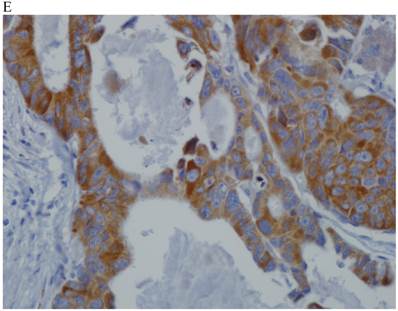

In the normal colonic mucosa, SDC1 is expressed at the basolateral membrane of the crypt epithelium and in the plasma cells of the lamina propria (Fig. 1A). In the colon cancer specimens, SDC1 staining results were available in 219 cases. Of these, positive SDC1 immunoreactivity was identified in the cancer cells of 212 cases (96.8%) of colon cancer. Of the SDC1-positive cases, 131 predominantly showed membranous immunopositivity, and 81 cases showed a predominantly cytoplasmic staining pattern. Exclusively cytoplasmic or membranous staining was observed in 28 and 30 cases, respectively. There were 154 cases, which showed a mixed membranous and cytoplasmic staining pattern (Fig. 1B-1E). In 93 cases, stromal SDC1 reactivity was noted (Fig. 1F). Epithelial SDC1 immunopositivity was significantly associated with an advanced primary tumor (T stage; p = 0.016) and EGFR immunohistochemical positivity (p = 0.006). In contrast, SDC1 expression was not significantly correlated with lymph node metastasis, distance metastasis, lymphatic or vascular invasion, or KRAS mutation states. Stromal SDC1 immunopositivity was significantly associated with the male sex (p = 0.018) and marginally associated with distant metastasis (p = 0.072). These findings are summarized in Tables 1 and 2. In addition, in the epithelial SDC1 immunopositivity cases, we evaluated which expression patterns, namely membranous or cytoplasmic, were significantly associated with various clinicopathological or molecular parameters. Membranous SDC1 immunopositivity, including a predominant and exclusive expression pattern, was significantly associated with advanced primary tumors (p = 0.001) and EGFR immunohistochemical positivity (p = 0.016). Moreover, membranous SDC1 immunoreactivity was significantly associated with stromal SDC1 immunohistochemical positivity (p = 0.021). In contrast, membranous or cytoplasmic SDC1 expression was not significantly correlated with other clinicopathological parameters or the KRAS mutation state (Table 3).

Representative syndecan-1 (SDC1) immunohistochemical staining in (A) normal colonic mucosa (× 200) and colorectal carcinoma with (B) only membranous staining (× 400), (C) predominantly membranous staining (× 400), (D) only cytoplasmic staining (× 400), and (E) predominantly cytoplasmic staining (× 400) staining patterns. (F) A case showing SDC1 immunopositivity in the stromal spindle cell component of tumor nests (× 200).